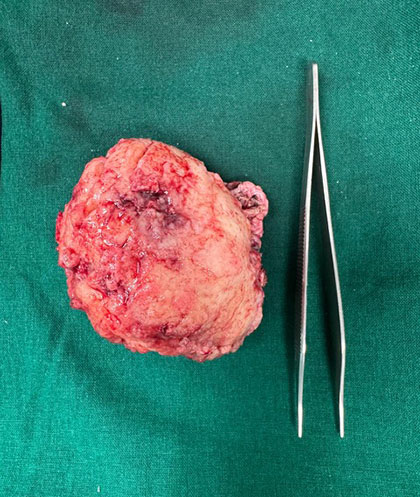

Dr. Ujwal Yeole is an experienced neurosurgeon specializes in treating a wide spectrum of neurological conditions including neuro-oncology, peripheral nerve disorders, vascular disorders, spinal pathologies, pediatric neurosurgery, neuro-trauma and skull base neuroendoscopic procedures.